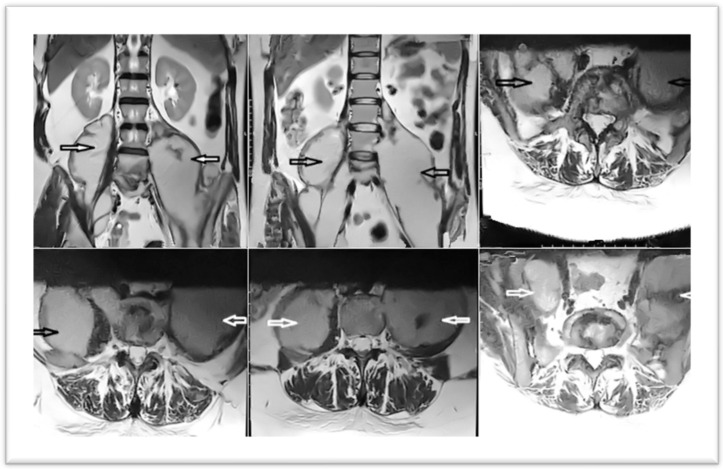

Background and Clinical Significance: Iliopsoas abscess has recently become a condition quite frequently present in our practice, arising through hematogenous or lymphatic dissemination (primary), or secondary to trauma or infectious-inflammatory vertebral, renal, or gastrointestinal diseases. It is often diagnosed with difficulty, due to the insidious and rather atypical symptomatology. The simultaneous relevance to neurosurgery, orthopedics, urology, rheumatology, and of course surgery, makes the iliopsoas abscess a real challenge in diagnosis and treatment for any of us, as well as collaboration between specialties. Case Presentation: The aim of this paper is to illustrate all this through a rare clinical case of vertebral tuberculosis, with giant abscesses of bilateral iliopsoas and comparison with data from the literature, through a review. Conclusions: The problems were related to the clinical-paraclinical, etiological diagnosis, surgical strategy, technique and tactics, surgical approach, treatment and immediate, and both long-term postoperative management. The ultimate goal is to reduce morbidity and mortality secondary to this often-disabling condition.